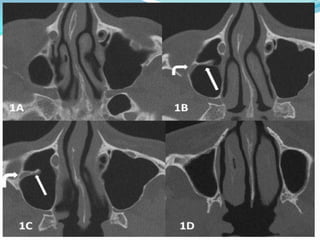

• #50 Axial CT scan slices, from top to bottom. A. Upper part of the maxillarysinus.B,C, slightly below A: the septum (straight arrow ) starts from the lateral sinuswall. Within it the infraorbital nerve (curved arrow) .D: lower portion of the sinus , withoutseptum. CT parameters in both cases were the following: 64 slices MDCT , 0625 mmthin slices, 100 kV, 50 mA resulting in patient 1 in a CTD/vol of 2,74 mGy, DLP 37,5 mGycmand 1,5 mSev